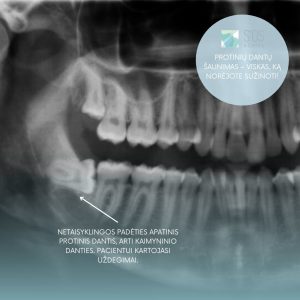

- Nėra vietos dantų lanke. Tuomet dantys išdygsta netaisyklinga kryptimi arba tik dalinai. Tokius apatinio žandikaulio dantis dažnai dengia dantenų „kapišonai“, kuriuose kaupiasi maistas ir bakterijos. Tokie dantys paprastai neatlieka kramtymo funkcijos

- Sukelia uždegimus arba spaudžia kitus dantis